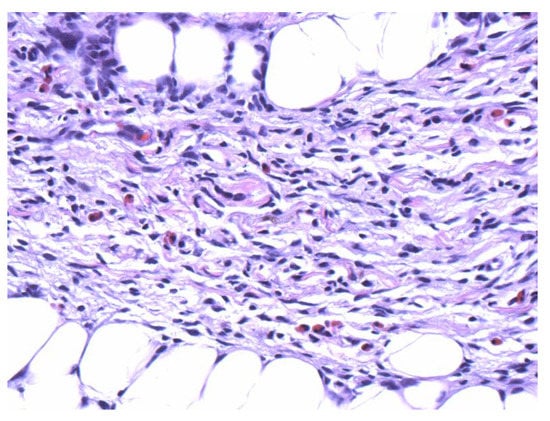

Figure 3.

Numerous eosinophils are scattered within the spindle cell proliferation (40×).